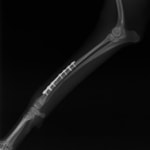

ペルシャ猫 11ヶ月齢 雄

他院にて左大腿骨遠位の成長板骨折(salter-harrisⅠ型)が認められており、治療相談を目的として来院。当院にて、キルシュナーワイヤーを用いたピンニングにより骨折部位の整復を行いました。術後の経過は良好で、現在も経過観察中です。

術後レントゲン

Arthrex社のターゲティングデバイスを用いてピンニングの位置を調整することで、確実な固定を行っています。当院ではこの手術器具以外にも、人の手術にも使用される様々な器具を導入し、手術精度を高め、また医療メーカーと新しい器具の開発、試作にも取り組んでおります。